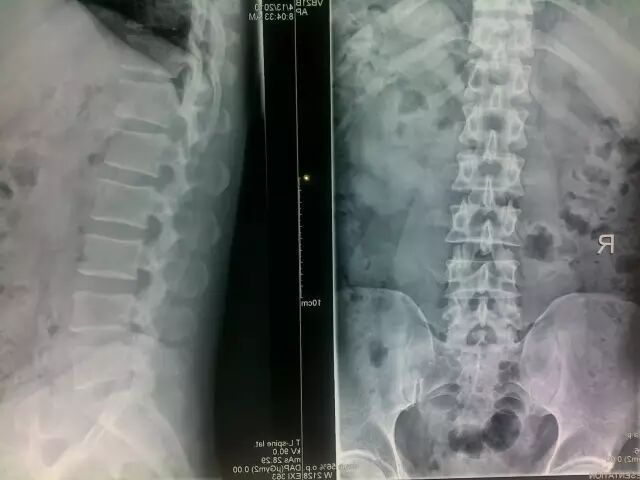

X片显示骨质及腰椎序列,不能显示椎间盘、脊髓及神经根等结构,只能通过间隙变窄来推断椎间盘病变可能。(约100元)